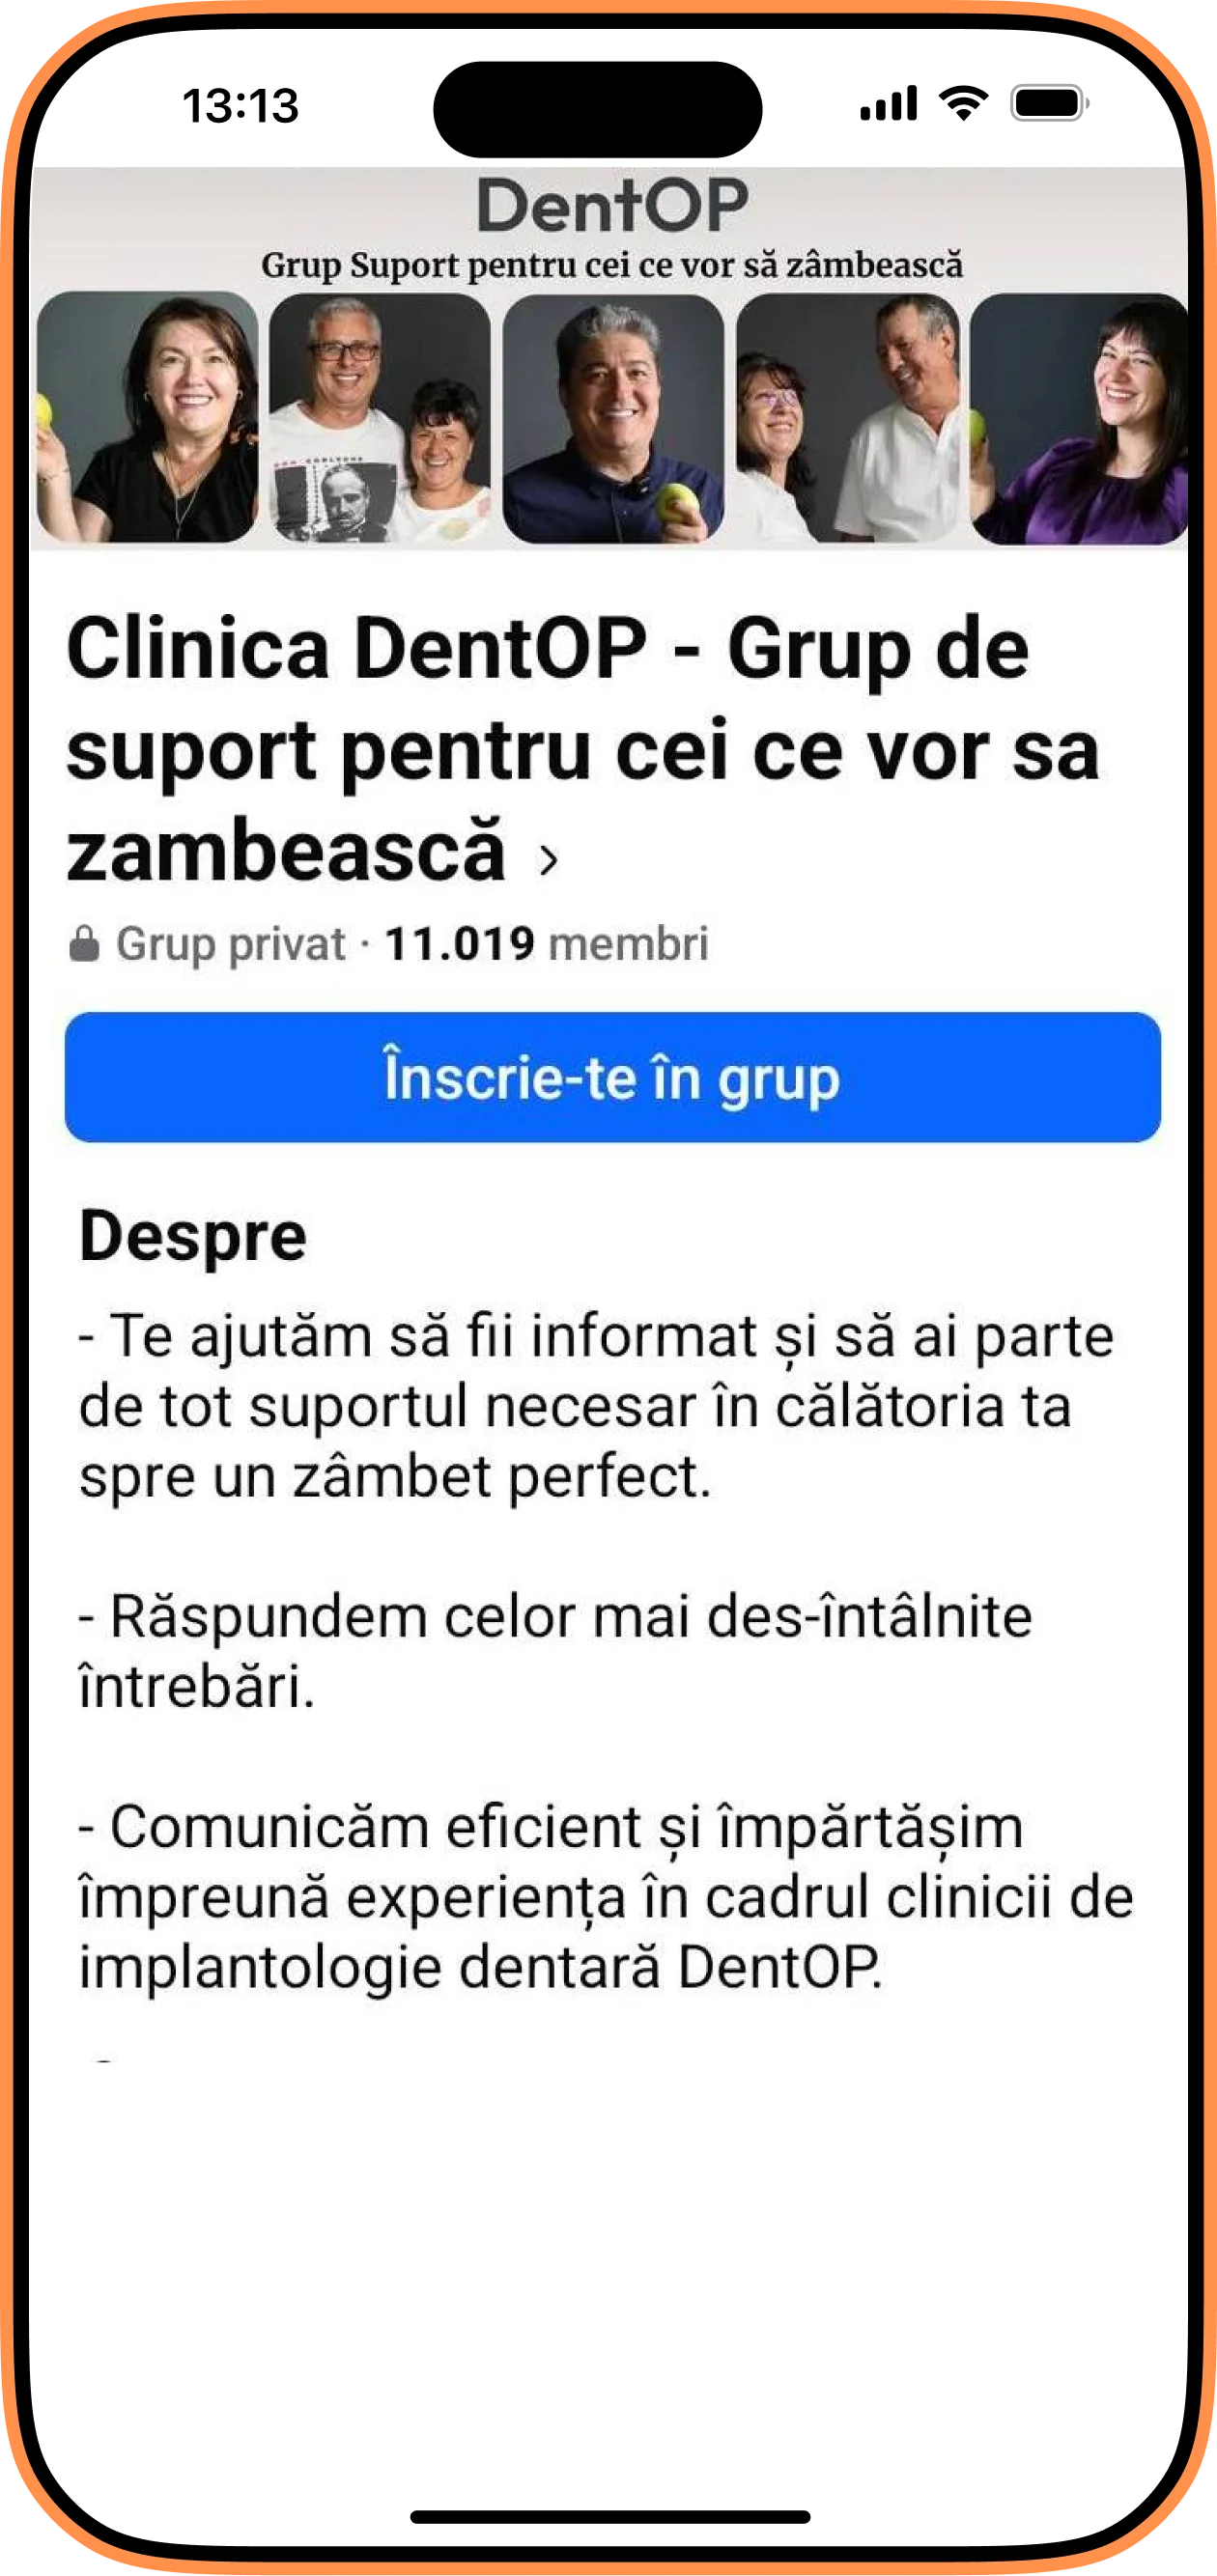

Doamna M. a venit cu o situație foarte complicată atât la maxilar, cât și la mandibulă. Mai multe chisturi și carii i-au afectat dantura considerabil. Boala parodontală se instalase în organism, iar soluția ideală oferită de Dr Cazacu Corrado – Medic Specialist Chirurgie Dento-Alveolară a fost trtamentul cu implanturi dentare.

În radiografia de mai jos, putem observa dantura inițială a doamnei Mihai , iar apoi la 6 luni de la intervenție cu 10 implanturi dentare inserate.